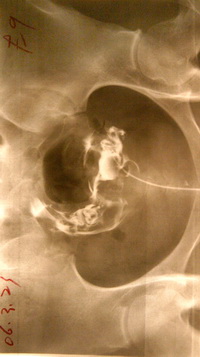

正常的输卵管造影图

输卵管根据其构造和功能,由前向后依次分为五部分:漏斗部——中央有输卵管腹腔口,边缘薄呈伞状。膨大部或称蛋白分泌部——是最长最弯曲的部分。峡部——为膨大部后方的缩细部分。子宫部——扩大成囊状,壁较厚。阴道部——变细弯曲成“S”形,后端开口于泄殖腔的左侧。